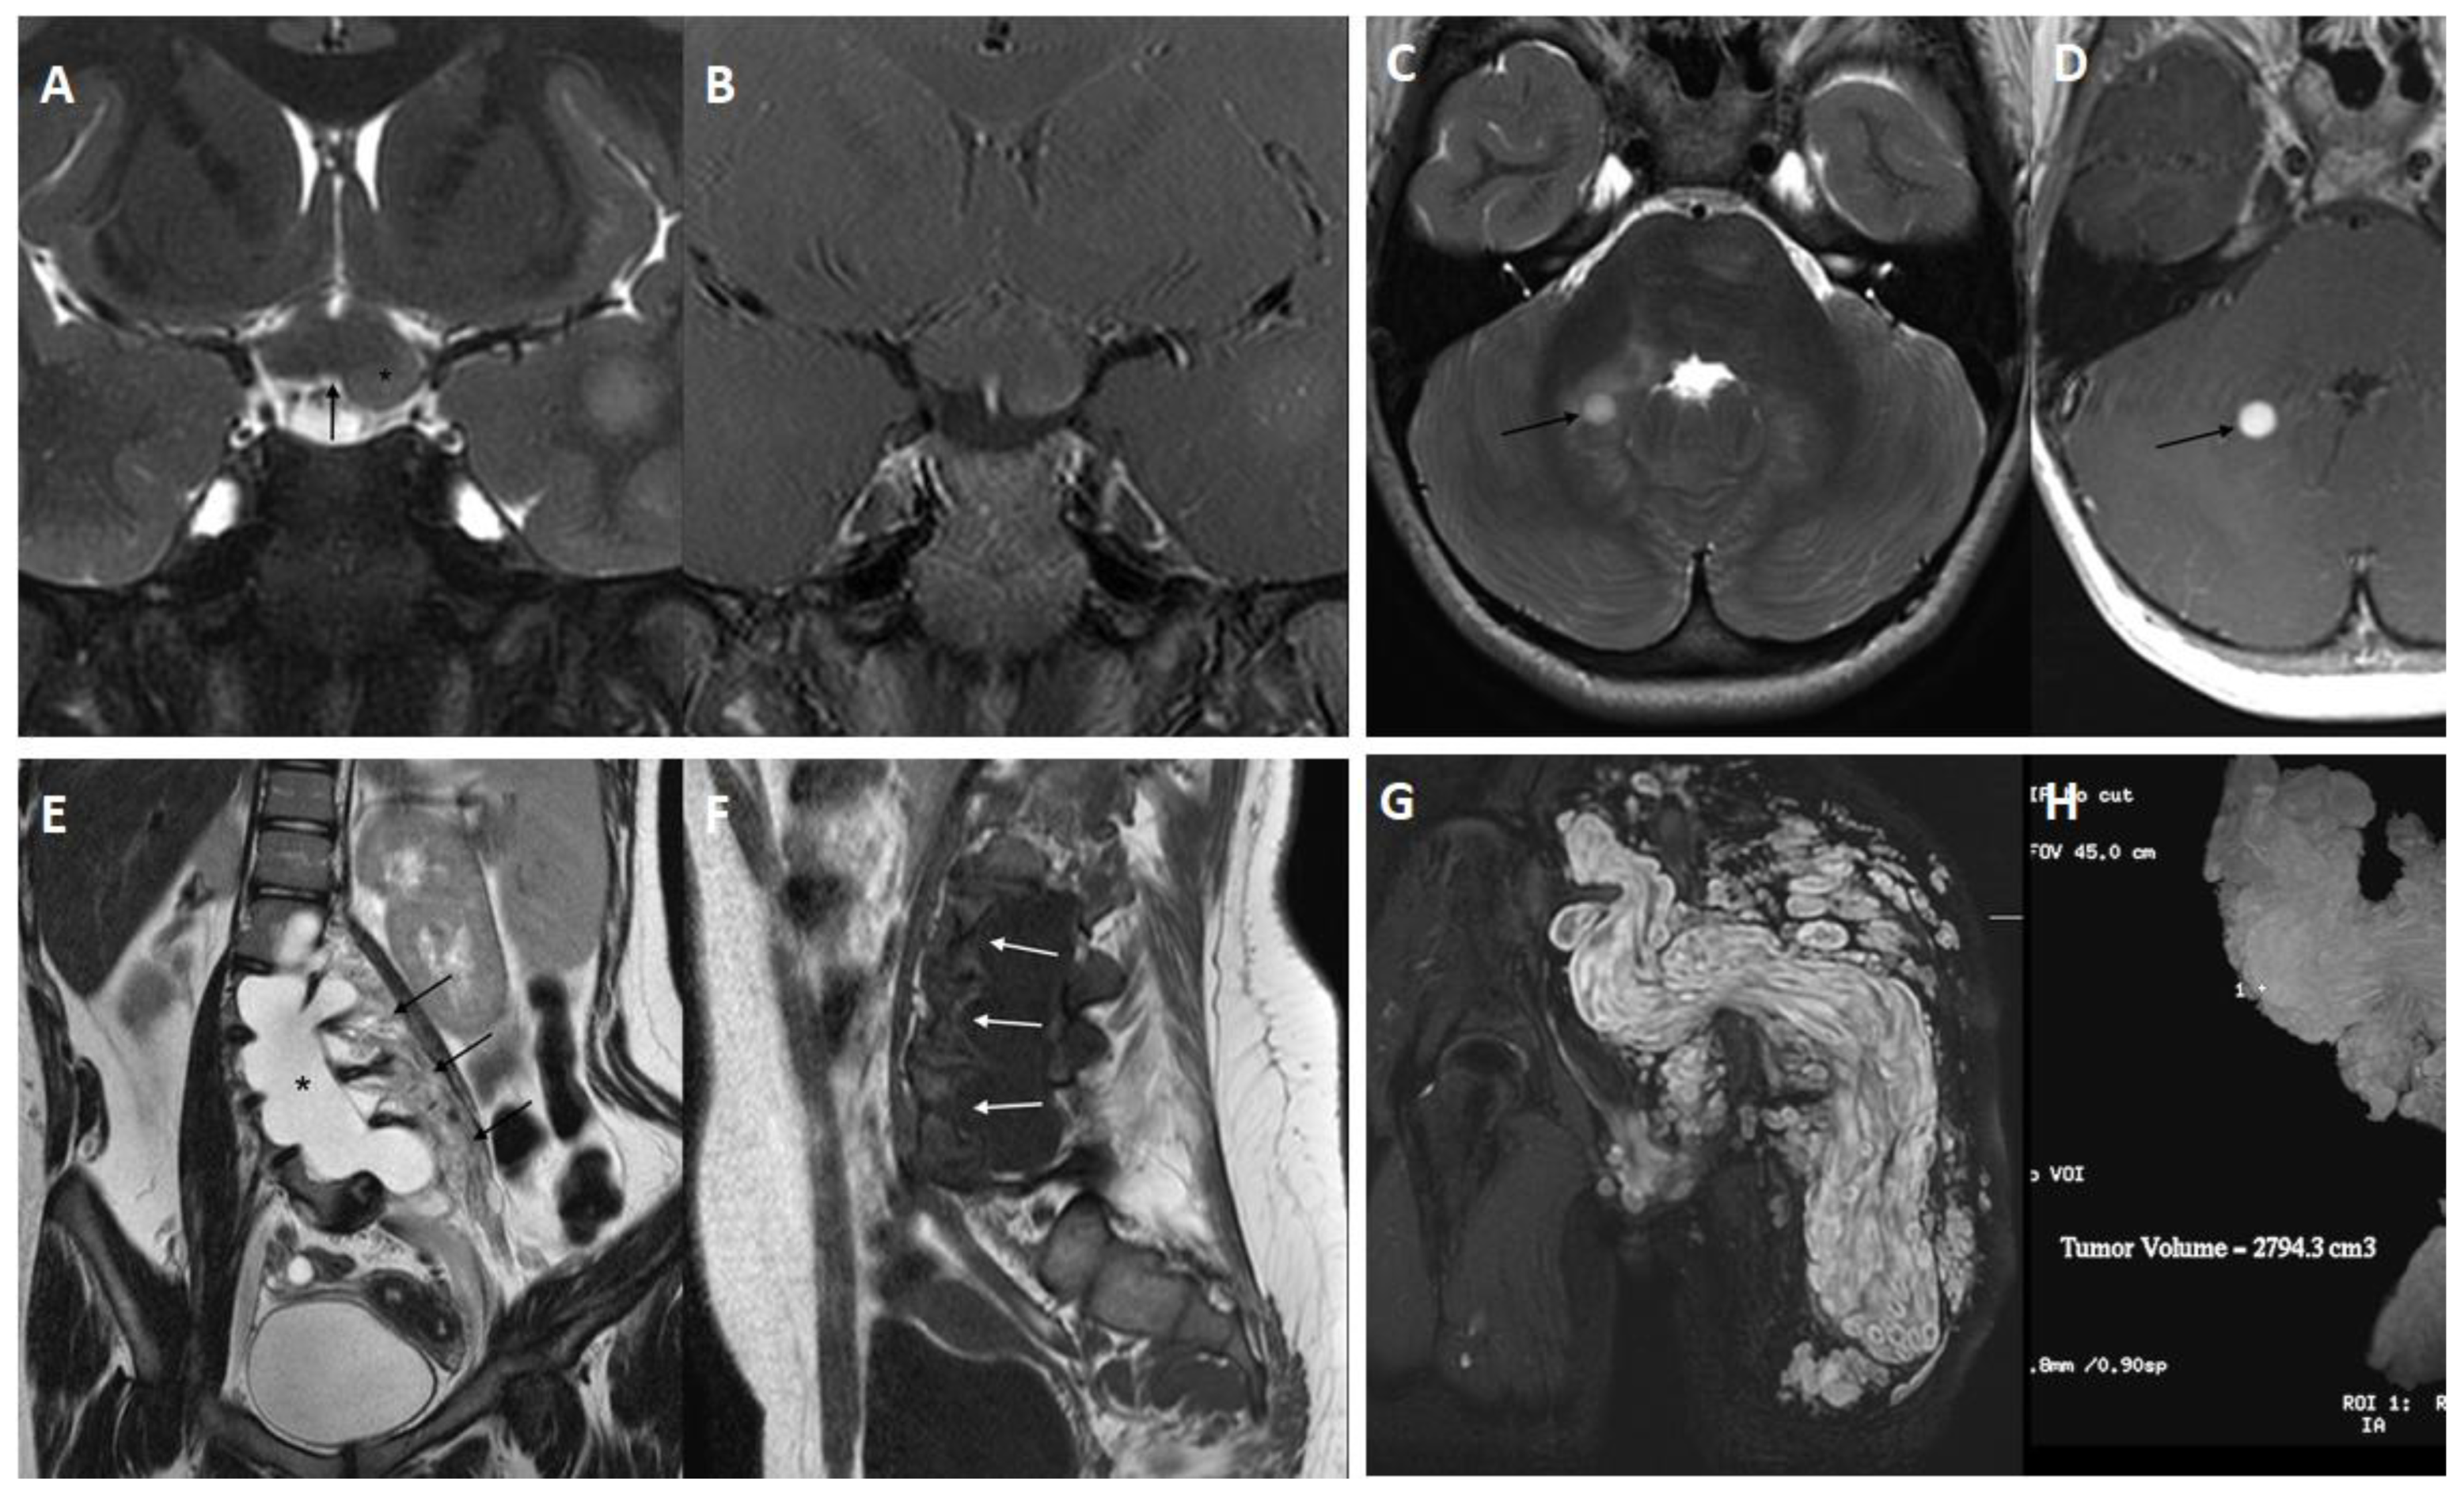

2.3. Tumors

- Santoro, C.; Picariello, S.; Palladino, F.; Spennato, P.; Melis, D.; Roth, J.; Cirillo, M.; Quaglietta, L.; D′Amico, A.; Gaudino, G.; et al. Retrospective Multicentric Study on Non-Optic CNS Tumors in Children and Adolescents with Neurofibromatosis Type 1. Cancers 2020, 12, 1426. [Google Scholar] [CrossRef]

- Shofty, B.; Barzilai, O.; Khashan, M.; Lidar, Z.; Constantini, S. Spinal manifestations of Neurofibromatosis type 1. Childs Nerv. Syst. 2020, 36, 2401–2408. [Google Scholar] [CrossRef]

- Khajavi, M.; Khoshsirat, S.; Ahangarnazari, L.; Majdinasab, N. A brief report of plexiform neurofibroma. Curr. Probl. Cancer 2018, 42, 256–260. [Google Scholar] [CrossRef]